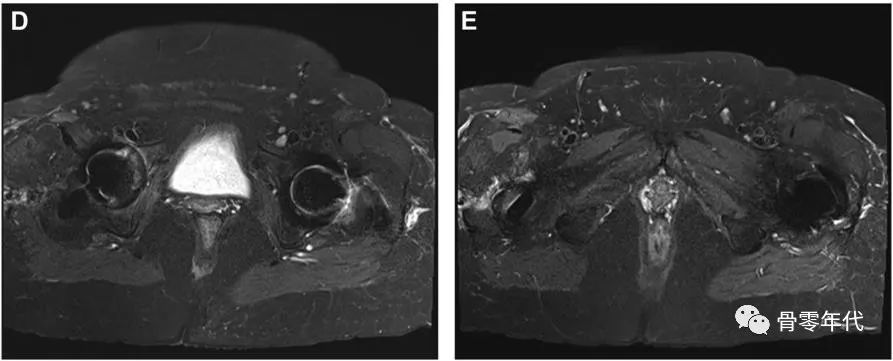

(A-C)术前X光显示左侧股骨近端骨量减少,翻修时预先放置的模块化骨干接合股骨柄用于假体周围骨折的治疗。(D和E)在外展肌重建前进行的MRI图像显示臀中肌和小肌脂肪萎缩,股骨肌腱附着处改变。(F和G)外展肌重建18个月后的部分MRI图像显示臀中肌附着完整,臀小肌部分连续。患者报告的外展肌重建术23个月的结果包括:静息疼痛,1/10;行走疼痛,3/10;Harris髋关节评分,61;牛津髋关节评分,22。患者报告中度跛行,仅需长时间步行时需要拐杖。

(A-C)术前X光显示大转子有轻微骨折,和先前植入的右全髋关节假体,包括非骨水泥的股骨柄和非骨水泥的髋臼假体。(D和E)在外展肌重建前进行的MRI图像显示臀中肌腱仍然附着在大转子骨折片段上。这块骨折碎片已经移位,近端移位。臀小肌腱终止于股骨近端的软组织。外展肌重建术后18个月的报告包括:休息疼痛,3/10;行走疼痛,8/10;Harris髋关节评分,26;牛津髋关节评分,37。患者报告中度跛行,行走时使用助行器。

(A-C)术前X光显示先前植入的右侧全髋关节假体,包括非骨水泥的股骨柄和非骨水泥的髋臼假体。(D和E)外展肌重建后12个月MRI图像显示臀中肌、臀小肌、臀大重建瓣和阔筋膜张肌重建瓣完整。患者报告的外展肌重建术22个月的结果包括:静息疼痛,1/10;行走疼痛,3/10;Harris髋关节评分,58;牛津髋关节评分,23。病人报告说,走路时有轻微的跛行和拐杖。